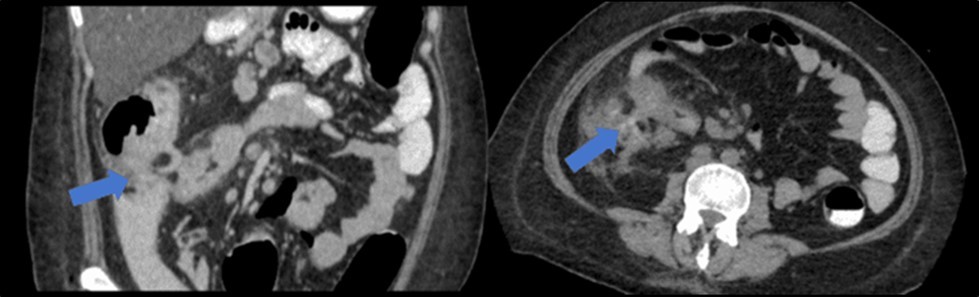

There was no evidence of malignancy or IBD seen during both endoscopic procedures. Computed tomography (CT) scan of the whole abdomen was done which showed inflammatory changes involving the cecum and adjacent duodenum and ileum with coloenteric fistulae. There was noted progression of abdominal lymphadenopathies as well as ascites. Main consideration was an infectious disease process (i.e. TB) (Figure 2, Figure 3, Figure 4 to Figure 5).

Figure 3.Coronal and axial view of the abdomen, the blue arrows pointing towards the suggestive communication to the ileum.

Coronal and axial view of the abdomen, the blue arrows pointing towards the suggestive                     communication to the ileum.